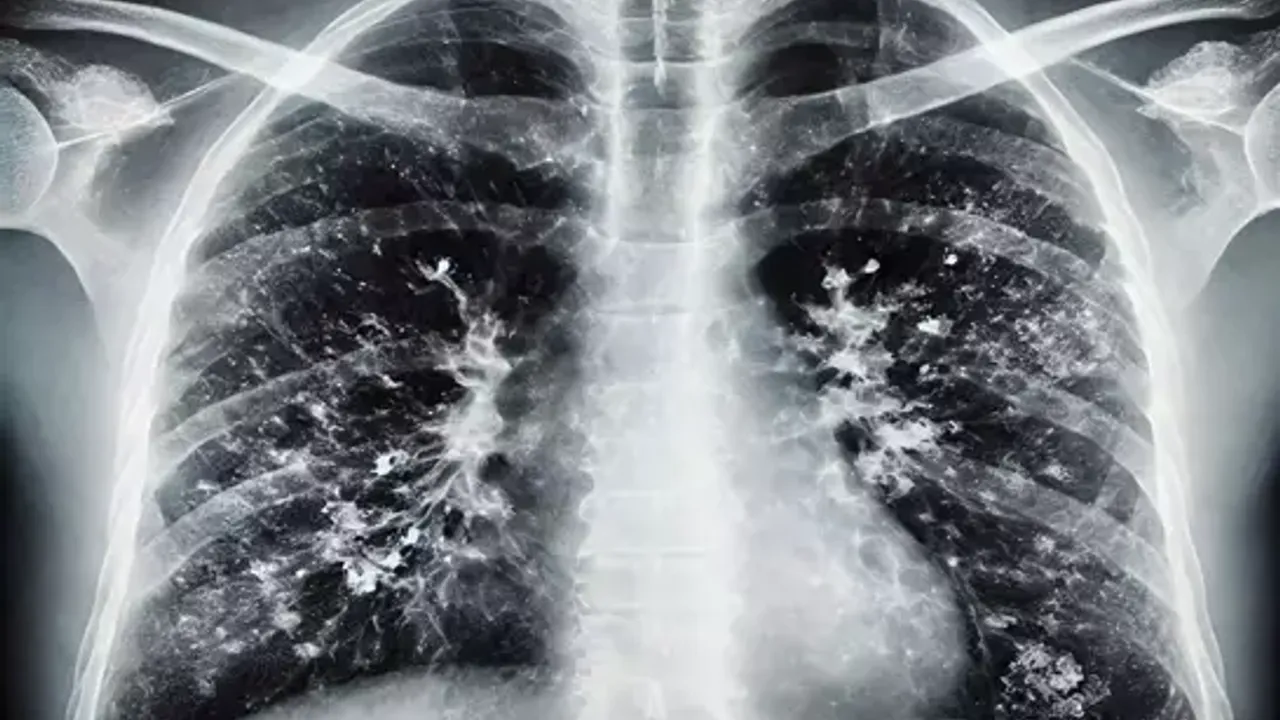

Solunum yolu enfeksiyonlarının çoğunlukla virüs kaynaklı olduğunu ifade eden Doktor Kızılelma, hasta kişilerin kapalı alanlarda maske kullanmasının bulaş riskini düşürdüğünü belirtti. Sağlıklı bireylerin de kalabalık ortamlarda maske takmasının koruyucu olabileceğini dile getiren Kızılelma, kişisel hijyenin en temel korunma yöntemi olduğuna dikkat çekti. Özellikle el yıkamanın hayati önem taşıdığını vurgulayan Kızılelma, ellerin yalnızca suyla değil, sabunla ve en az 20 saniye boyunca ovuşturularak yıkanması gerektiğini, ardından mutlaka kurulanmasının önem taşıdığını söyledi.